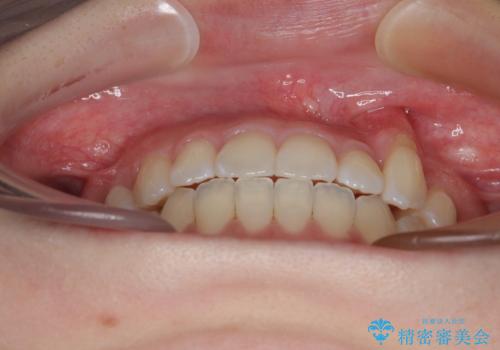

急速拡大装置 狭い上顎骨を拡大してワイヤー装置で八重歯を短期間治療

- 上顎の八重歯やデコボコを気にして来院された患者様です。

上顎歯列が狭窄していたため、急速拡大装置により上顎骨を側方に拡大しながら、ワイヤー装置にて矯正治療を行うこととしました。

上顎骨を拡大することで、八重歯やデコボコを歯列に収めることができ、下顎の歯が外に位置していた奥歯の咬み合わせも改善することができました。